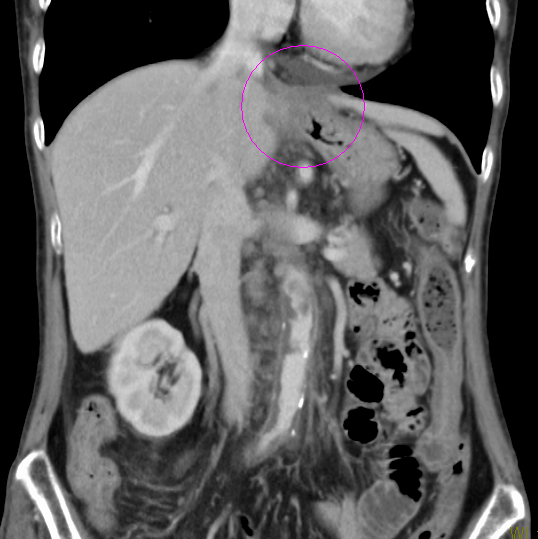

術前化学療法の例(造影CT画像)

治療後